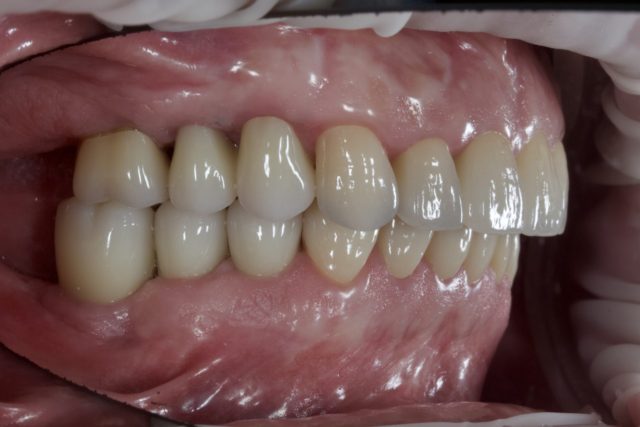

AFTER